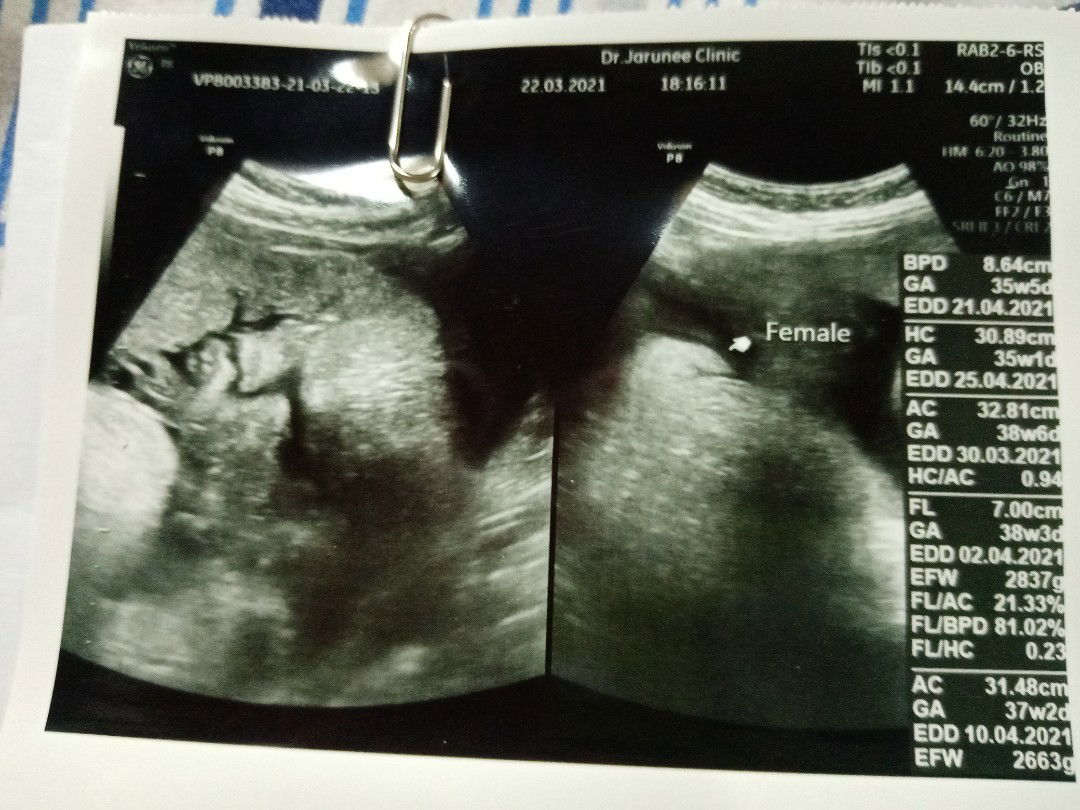

วันนี้ไปซาวมาคุณหมอบอกว่ารกพันคอลูกเราตกใจมากแต่หมอบอกว่าแค่รอบเดียวไม่เป็นไรเราควรทำอย่างไรดีค่ะ

#ขอคำแนะนำหน่อยค่ะ

การนับลูกดิ้นสำคัญมากค่ะ